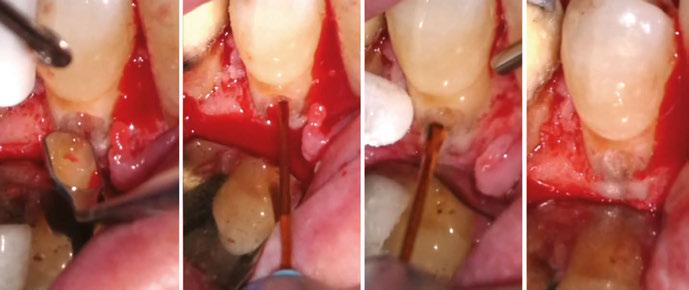

on the crest of the ridge in the region of teeth Nos. 15-25. While creating the incision, bleeding was noticed in the region of tooth No. 15 which intensified during the flap reflection (Figure 2). Bleeding was pulsatile, indicating an arterial bleed. Initially attempts to control bleeding included a pressure pack and ice pack, and the bleeder was isolated, and the vessel ligated (Figure 3). The bleeding could be controlled, and the procedure was completed by placing four Bioner implants (Bioner, Spain), size 4/10 mm. Sutures were placed, and patient was kept on basic medication for pain and infection control. Immediately after the surgery, the patient was advised to get a CBCT. As shown in Figure 4, a coronal view and Figure 4B (yellow arrows), the position of the artery can be seen.

Figure 1: Pre-op panoramic radiograph Figure 2 (left): Alveolar antral artery (AAA). Figure 3 (center): The artery has been ligated with suture. Figures 4A and 4B (right): CBCT post-implant placement and position of the artery coronally (top). 4B. Showing the position of alveolar antral artery (AAA) in relation to implant placement as indicated by the yellow arrows (bottom)